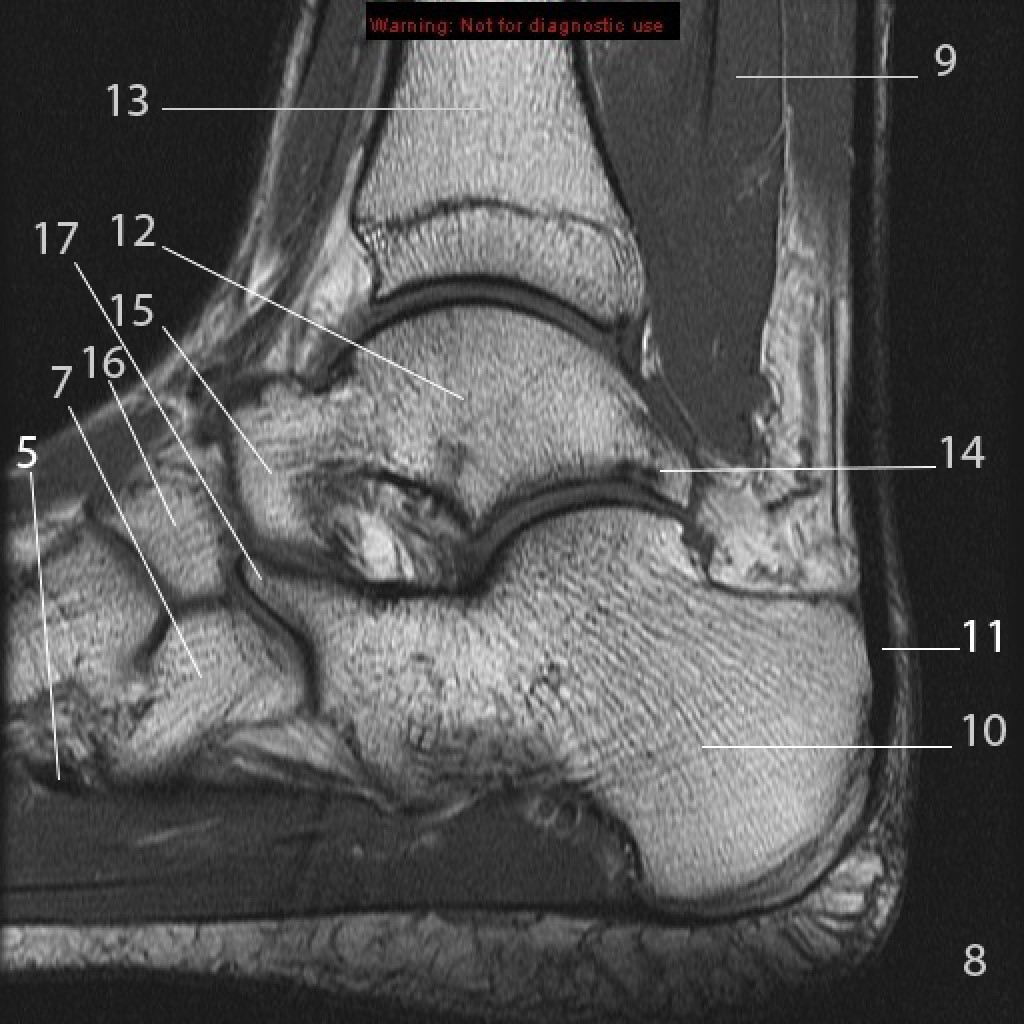

Анатомические фото голеностопного сустава и его суставных поверхностей